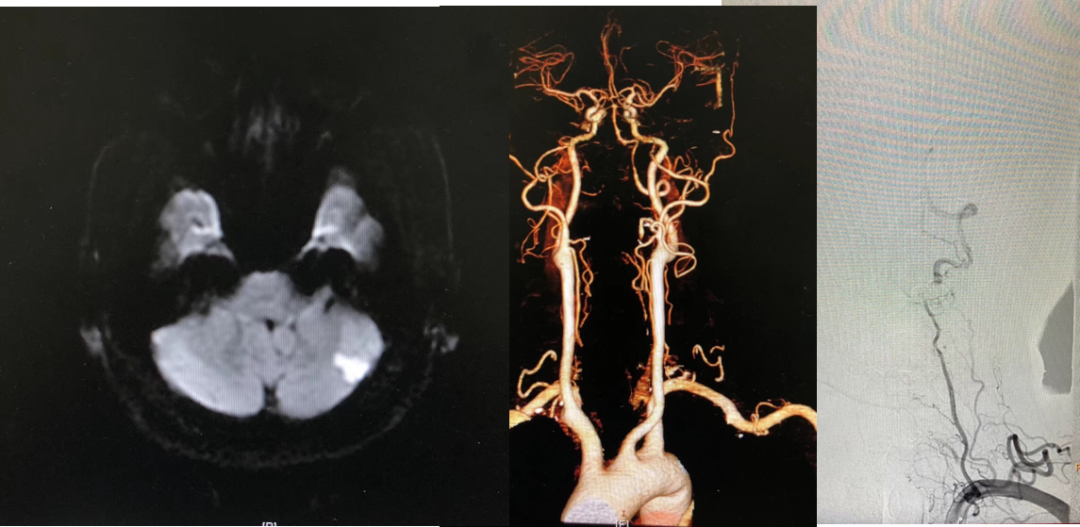

M,60,左侧小脑梗死,左椎动脉V1-V2段长段闭塞

案例二

左椎V1-V2闭塞 开口自体静脉补片成形

案例三

左椎V1-V2闭塞 椎-甲状颈干补片搭桥

14个月复查

案例四

椎动脉支架内再狭窄